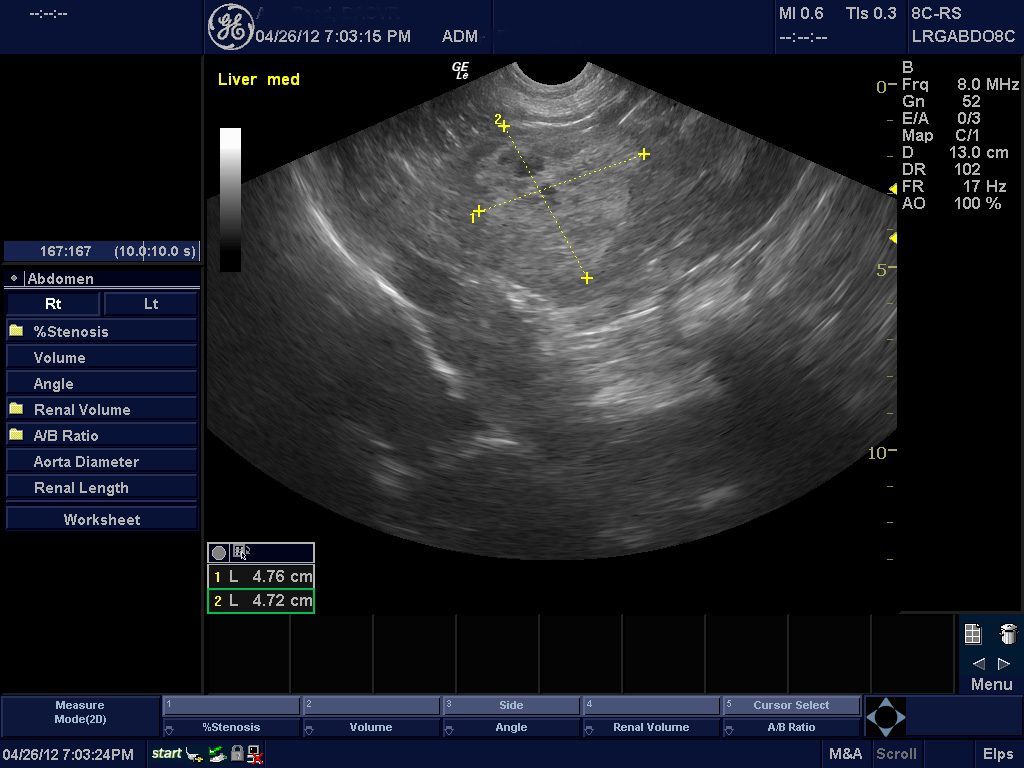

Kidney Disease- Renal Dysplasia or Glomerulonephritis

Shih Tzus can develop kidney disease (renal dypsplasia) early on in life, which verifies the importance of routine exams on a yearly basis. The initial symptoms of this disease are subtle, consisting only of a mild increase in thirst and urination. Due to this subtle nature, it is a good idea to quantify how much water you put in your pets bowl everyday. This problem is diagnosed with a blood sample, a urinalysis, radiographs, and especially, ultrasound.

The diagonal line in this ultrasound demarcate the renal pelvis, and is checking for renal dysplasia